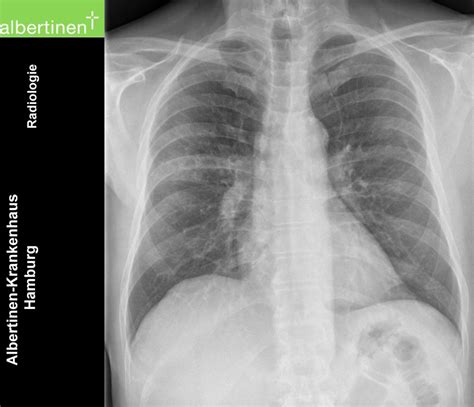

When to See a Doctor

Although the condition is mild, it should not be ignored. You should seek medical attention if you experience difficulty breathing, a persistent high fever, or if your cough worsens significantly. A healthcare provider can perform a physical examination, listen to your lungs, and potentially order a chest X-ray or a lab test to confirm the diagnosis. Early intervention can help manage symptoms more effectively and reduce the time you remain infectious to others.